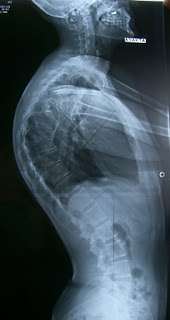

Рентген грудного кифоза: степени и диагностика